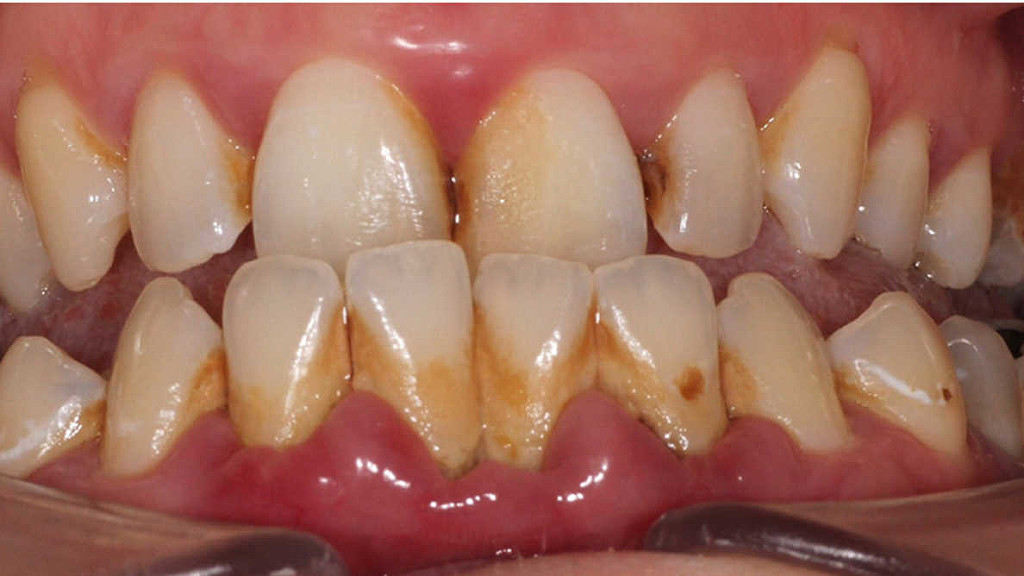

Oral biofilms, a concern for all dental professionals

Biofilms are a collective of one or more types of microorganisms that can grow on many different surfaces. Microorganisms that form biofilms include bacteria, fungi and protists.

One common example of a biofilm dental plaque, a slimy buildup of bacteria that forms on the surfaces of teeth. Pond scum is another example. Biofilms have been found growing on minerals and metals. They have been found underwater, underground and above the ground. They can grow on plant tissues and animal tissues, and on implanted medical devices such as catheters and pacemakers.

Role of oral biofilm in the aetiology of disease:

Oral biofilm is medically important because it has broad implications for maintaining not only oral health but also systemic health. It is estimated that biofilms account for over 80% of microbial infections in the body. Research has undoubtedly shown that biofilm-dependent infections, including oral diseases such as caries, and periodontal and endodontic disease, thus pose major public health and cost concerns globally.

Periodontal disease, in particular, is considered one of the most prevalent diseases worldwide, affecting up to 50% of the world’s adult population, according to FDI World Dental Federation. Previous research has established connections between periodontal disease and preterm births, low birthweight, diabetes, and risk factors associated with cardiovascular disease and stroke. Globally, periodontitis is responsible for an estimated US$54 billion per year in lost productivity and a major portion of the US$442 billion spent annually on oral disease, according to the European Federation of Periodontology.